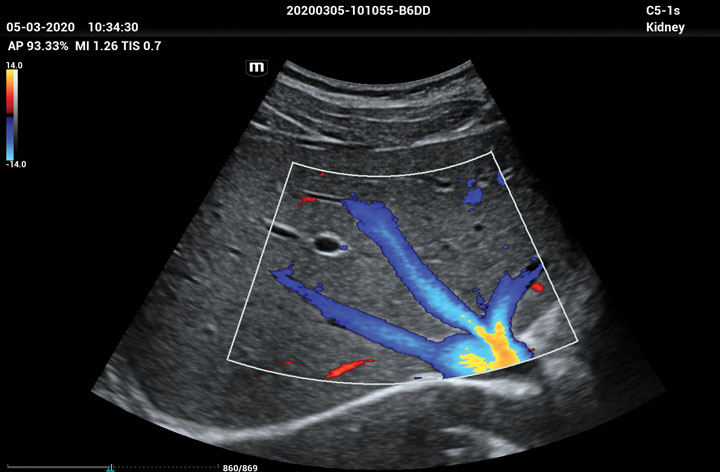

The ME8 Ultrasound System has been thoughtfully designed to overcome the obstacles clinicians face in today’s challenging healthcare environment. Powered by our groundbreaking software-based beamformer technology, ZONE Sonography® Technology+(ZST+), the ME8 Ultrasound System empowers decision-making by providing end-users best-in-class image quality and access to a comprehensive suite of workflow enhancement tools.